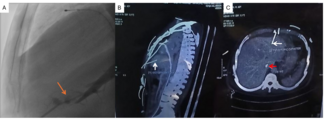

The J-Channel score (adjusted for septal and non-septal scores, accordingly) was negatively associated with the likelihood of successful wire crossing (odds ratio [OR]: 0.62 per 1 score unit increase; 95% CI, 0.57-0.67; P < .001) and successful microcatheter crossing (OR:0.62 per 1 score unit increase; 95% CI, 0.56-0.67; P < .001). When compared with the derivation population, the PROGRESS-CTO patients had lower CC wire crossing success for easy difficulty grade based on both septal and non-septal J-Channel scores, and higher CC wire crossing success rates for intermediate and difficult grades (Figure, A and B). The AUC of the J-Channel score was 0.653 (95% CI, 0.628-0.678) for successful wire crossing (Figure, C), and 0.654 (95% CI, 0.629-0.680) for successful microcatheter crossing (Figure, D). The model showed satisfactory goodness-of-fit (Hosmer-Lemeshow P = .59, P = .52; respectively) (Figure, E and F). Interrater reliability resulted in a moderate level of agreement between 3 observer groups for septal J-Channel score (Kappa = 0.415; 95% CI, -0.278-1.108; P < .001) and non-septal J-Channel score (Kappa = 0.432; 95% CI, -0.372-1.236; P < .005).